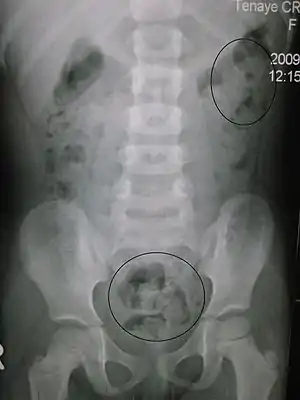

| Constipation in a young child seen on X-ray. Circles represent areas of fecal matter (stool is white surrounded by black bowel gas). | |

Abdominal X-rays are generally only performed if bowel obstruction is suspected, may reveal extensive impacted fecal matter in the colon, and may confirm or rule out other causes of similar symptoms.[24][16]